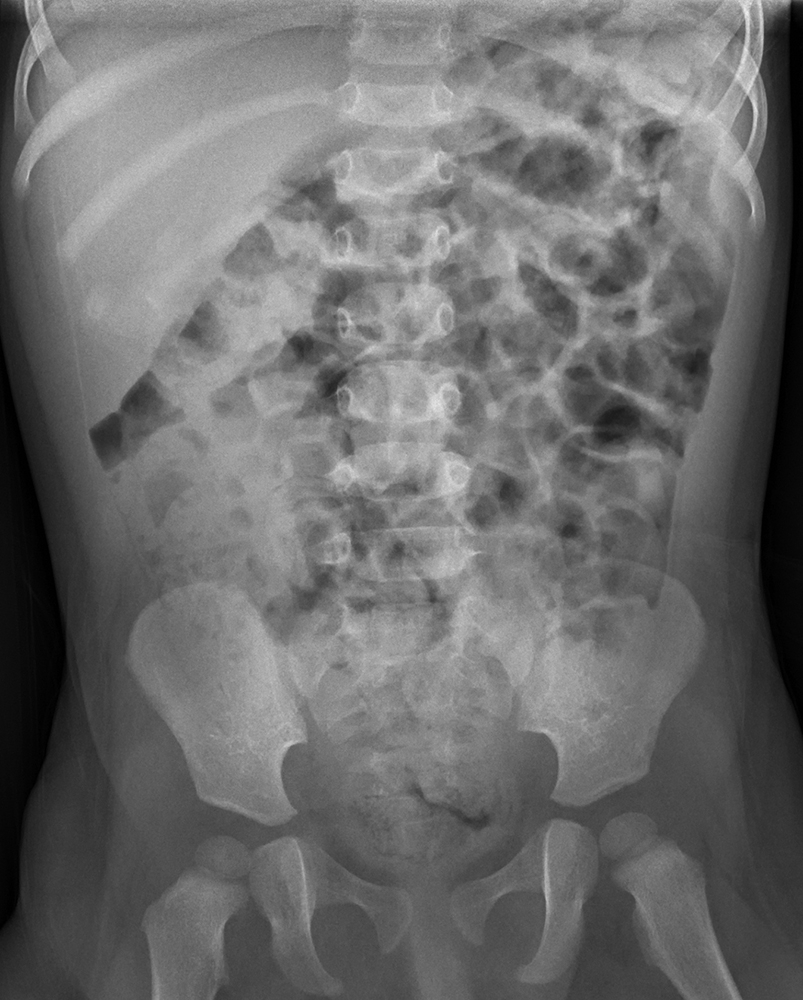

The nonobstructive bowel gas pattern appears as a normal arrangement of gas bubbles within the intestines. It shows that the intestines are functioning properly and that there are no blockages or abnormalities that could cause digestive issues.

In some cases, a nonobstructive bowel gas pattern may be seen in patients who are experiencing symptoms like bloating or abdominal pain. While this finding is reassuring, it’s essential for healthcare providers to consider other factors and conduct further tests if needed to determine the root cause of these symptoms.